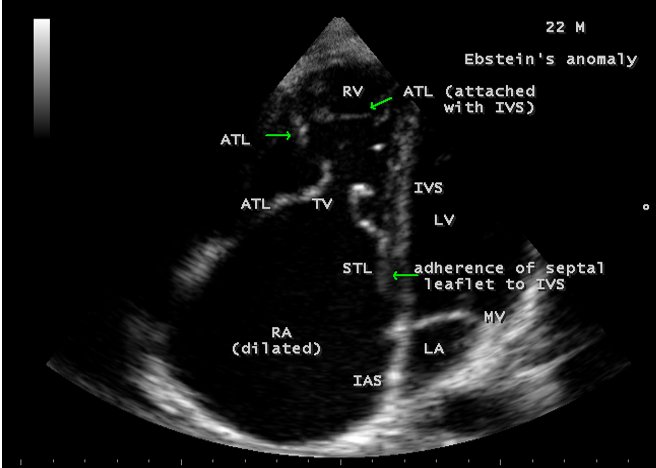

A 22-year old acyanotic male was presented with features of right heart failure and a grade 3/6 systolic murmur at lower left sternal border. 2D echocardiography revealed a normally attached septal tricuspid leaflet (STL), but tethered to the ventricular wall suggesting an Ebstein’s anomaly with severe tricuspid regurgitation swirling around the lateral wall of right atrium and interatrial septum, and a dilated atrium and atrialized RV (right ventricle) as shown in Figures 4 to 8.

Echocardiographic features Echocardiography is the diagnostic test of choice for Ebstein’s anomaly and the first echocardiographic diagnosis was reported by Lundstrom in 1969. The first diagnostic criteria for Ebstein’s anomaly using a multi-crystal two-dimensional system was defined by Hagan in 1974 [33] and they were able to recognize the apical displacement of the septal tricuspid leaflet and an elongated anterior tricuspid leaflet with increased excursion. The septal leaflet of the tricuspid valve attaches chiefly to the ventricular septum , but part of its basal attachment is to the posterior wall of the right ventricle [34] and it normally exhibits a slight but distinct apical displacement of its basal attachment to the central fibrous body compared to the mitral valve. The distal displacement of septal origin of tricuspid valve seems to be the best echocardiographic criterion as the characteristic sign for Ebstein’s anomaly and the degree of maximal displacement in normal hearts varies considerably with a mean difference of approximately 6 mm with mitral valve. To define the anatomic severity of Ebstein’s anomaly, four-chamber view is the best to demonstrate the apical displacement of septal tricuspid leaflet [35]. The ratio between the mitral-to-apex distance and the tricuspid-to-apex distance varies from 1 to 1.2 in normal subjects and 1.8 to 3.2 in patients and it is 3.6 as in Figure 18 with Ebstein’s anomaly. The true distance in the level of insertion of atrioventricular valves is obtained by substracting the tricuspid-to-apex distance from the mitral-to-apex distance with a mean value of 27.25 ± 12 mm in patients with proven Ebstein’s anomaly and it is 60 mm as shown in Figure 18 compared to reference group (5.7 ± 2 mm). Kambe and coworkers calculated the distance between both atrioventricular valves directly as a mean value of 21 mm with a range of 14 to 32 mm [36]. A maximum difference in the level of valve insertion of >15 mm in children and >20 mm in adults is discriminated between normal and Ebstein’s anomaly [37],[38]. Despite this fact, a patient with an ‘unequivocal’ Ebstein’s malformation can be encountered in whom the diagnosis cannot be made with certainity solely on the basis of apical displacement of the septal tricuspid valve leaflet. Occasionally, the leaflet attaches to the trabecular part rather than the inlet part of the septum, the conventional four-chamber view will not reveal any septal insertion as shown in Figures 28 and 29.

The anterior tricuspid leaflet is not involved in the process of downward displacement, it may be abnormally inserted occasionally and Shiina, et al documented the apical displacement of anterior tricuspid leaflet in 14% of cases echocardiographically [39]. The anterior leaflet forms a large, sail-like intracavitary curtain as in Figures 14, 25 and contains muscular strands instead of consisting entirely of a fibrous membrane as in the normal tricuspid valve [40]. It is potentially mobile with a brisk sail-like movement as shown in Figure 21 to 24 [41], free bloating with a ‘whipping motion’ across the right ventricular outflow tract (RVOT) as shown in Figure 26 and in some cases, the movement is restricted due to its adherence to the ventricular wall as in Figure 1 and 2, 4 and 9. It is often fenestrated, may in part be musculaized , inserting into the trabeculations of the right ventricle (RV) as in Figure 28 and rarely, the anterior leaflet forms an ‘atretic’ membrane that spans the midportion of the right ventricular cavity as in Figure 16.

In severe cases, the inferior wall of the right ventricle may consists soley of thin fibrous tissue, devoid of myocytes and thereby represent an area of aneurysmal dilatation as in Cases 2 (Figure 8) and 3 (Figures 20 and 24). It is apparently due either to slippage of right ventricular inflow tract away from the right atrioventricular junction or to focal excessive ‘undermining’ to myocardium, transmurally to the level of epicardium. A large atrialized area causes a severe reduction in the volume of the right ventricular pumping chamber and usually produces an abnormal configuration of muscular interventricular septum, which bulges leftward and thereby compresses the left ventricular chamber, resulting in reversal of ventricular shapes with a ‘circular’ right ventricle and a ‘banana’ [42] or ‘crescentic’ [43] left ventricle as shown in Figures 29 and 30 Thus, the proximal component of the right ventricle, the ‘inlet portion’ is the part directly involved with the malformation and the distal apico-trabecular and outlet portions that constitute the ‘functional right ventricle’, which is not involved and may be of normal size, but usually markedly diminished in dimensions and in some cases, it is dilated and thin walled.

The tricuspid orifice is typically incompetent as in Figures 3, 5 and 10, occasionally stenotic, and rarely imperforate as in Figure 16 [44],[45]. The true anatomic tricuspid annulus occupies its normal position at the right atrioventricular junction and it is less well defined than in a normal heart. The annulus tends to be appreciably dilated and contribute to the development of valvular incompetence. In extreme downward displacement of posterior and septal leaflets, the closure of the tricuspid annulus depends on the size and potential excursion of anterior leaflet. When the chordal attachments are short and the leaflets contain multiple or large fenestrations, adequate valve closure is impossible to achieve and varying degrees of regurgitation results. Color flow imaging and Doppler interrogation can establish the relatively low velocity regurgitant flow as in Figure 6, which begins at the level of the displaced septal and posterior leaflets as in Figures 5 and 10 and courses through the atrialized right ventricle into the right atrium proper as shown in Figure 5. Tricuspid regurgitation increases by annular dilatation [46]. During contraction of the atrium, the atrialized portion of the right ventricle balloons out and acts as a passive reservoir. Functional improvement of right ventricle depends on the severity of tricuspid regurgitation and on the ratio of the combined areas of right atrium and atrialized right ventricle relative to the areas of functional right ventricle and left ventricle [47]. Celermajer, et al described an echocardiographic grading score for neonates with Ebstein’s anomaly as shown in the Table 5 [48].

The functional impairement of right ventricle and regurgitation of tricuspid valve retard the forward flow and the overall effect is right atrial dilatation as shown in Figure 4. In many cases, the right atrial enlargement is extensive, but the mural thrombus is not a feature even in right ventricular dilatation. The enlarging right atrium becomes sufficiently compliant to accomodate a large volume of regurgitant flow with little or no increase in pressure as shown in Figure 6., In patients with marked Ebstein’s malformation and severe tricuspid regurgitation, liver and portal circulation are extensively affected, congestive hepatosplenomegaly and microscopic hepatic fibrosis eventually occurs in chronic cases with hypersplenism [49].